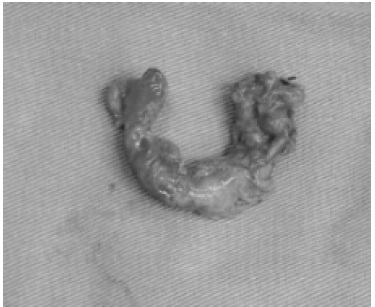

El paciente fue sometido a apendicectomía clásica con abordaje Rockey Davis, bajo técnica de Pouchet, durante la cual se observó un proceso inflamatorio del apéndice vermiforme gangrenosa con trayecto postileal adherido en un 70% a la serosa del borde antimesentérico del íleon distal con microperforaciones en la punta y con base sana, asociado a escaso líquido inflamatorio pericecal y periapendicular. Figura 1. Después de su hospitalización y manejo médico, el paciente fue dado de alta a las 48 horas, sin complicaciones.

En la valoración posterior, en el servicio de consulta externa, se reporta espécimen producto de apendicectomía que mide 7 cm x 1 cm x 1 cm en el estudio anatomopatológico, recubierto por una serosa despulida de color pardo oscuro. Figura 2. Al corte, la luz esta dilatada y ocupada por material fecaloide. El estudio histológico, reveló perdida de la histoarquitectura secundario a proceso inflamatorio agudo severo de distribución transmural y extensa necrosis, no hay malignidad.